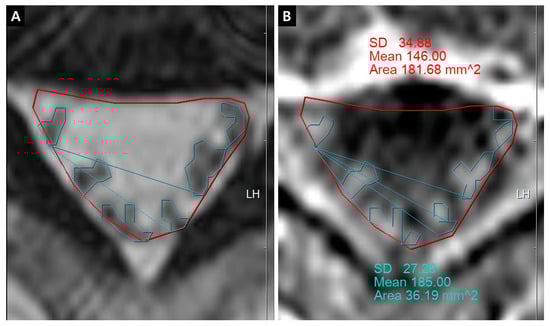

Figure 5. Whole rootlets IRCE (WR-IRCE) on L4–5 as a control. (A) T2-weighted axial image; (B) fat-suppressed enhanced T1-weighted axial image. SD—standard deviation

The quantification of IRCE was evaluated by the ratio (%) of signal intensities between the cauda equina and psoas muscle on the same axial enhanced image. The signal intensity of rootlets was measured within the manually defined region of interests (ROIs) along the boundary of the white signal by a digitizer, Maroview software (Infinitt Healthcare Co., Seoul, Korea). To define an exact margin, intrathecal rootlets were marked on the same T2-weighted axial image. The adjustment of the gray scale (window level) was necessary for the discrimination between the rootlets and cerebrospinal fluid. Manual ROI analysis was performed by superimposing previously acquired ROI on the enhanced fat-suppressed T1-weighted image (Figure 5). Two methods were composed of whole rootlets IRCE (WR-IRCE) and maximal spot rootlet IRCE (MS-IRCE) at the most stenotic level (Figure 6). WR-IRCE was obtained by recording the mean signal intensities of all outlined intrathecal rootlets. MS-IRCE was defined as the maximum value in circular ROIs (0.18 mm2) among intrathecal rootlets. In some patients, the large radiculomedullary veins showed strikingly higher signal intensities (>315) than those of other rootlets. These high signals were excluded in the subsequent measurements. The measurement of WR-IRCE and MS-IRCE on the L3–4 and L4–5 levels, respectively, were also performed in the asymptomatic control group to find a difference between such levels. The signal intensity measurement of the psoas muscle was performed within manually defined ROIs (Psoas1), which were delineated along the margin of the unilateral psoas muscle on the same enhanced axial images. In addition, circular ROIs (33.42 mm2, Psoas2) were designated within the medial portion of the psoas muscle corresponding to a mid to posterior disc space to avoid field inhomogeneity (Figure 7). Using these signal intensities, four rootlet-to-psoas ratios were defined (MS/P1 = MS-IRCE/Psoas1*100, WR/P1 = WR-IRCE/Psoas1*100, MS/P2 = MS-IRCE/Psoas2*100, WR/P2 = WR-IRCE/Psoas2*100). Those parameters were analyzed to identify the best possible candidate to stratify patients with lumbar central stenosis.